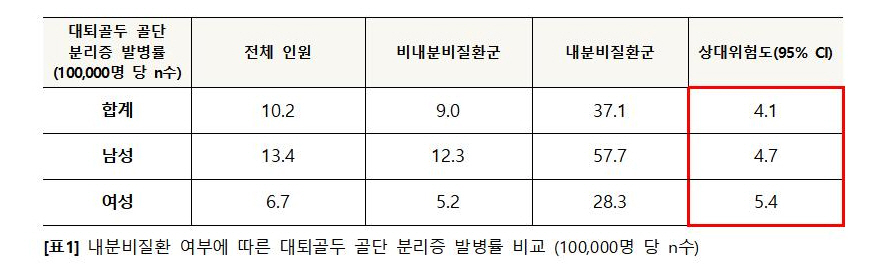

분석 결과, 내분비질환군은 비내분비질환군에 비해 대퇴골두 골단 분리증의 발병률이 약 4배 높았으며, 특히 여아의 경우에는 5.4배가 높은 것으로 나타났다.

[표1] 내분비질환 여부에 따른 대퇴골두 골단 분리증 발병률 비교 (100,000명 당 n수)